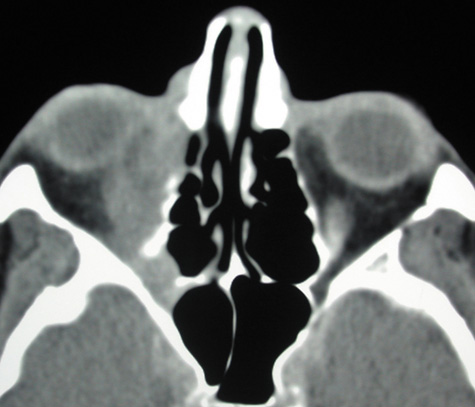

With preseptal inflammation, CT demonstrates soft tissue swelling of the eyelids and tissue adjacent to the orbital septum (Fig. 15). The orbit is not involved, and usually the sinuses do not show evidence of inflammation. The distinction between inflammatory preseptal cellulitis and edema cannot be made.63

Fig. 15. Computed tomography showing preseptal cellulitis of left eye. Note that all swelling is anterior to the orbital septum.